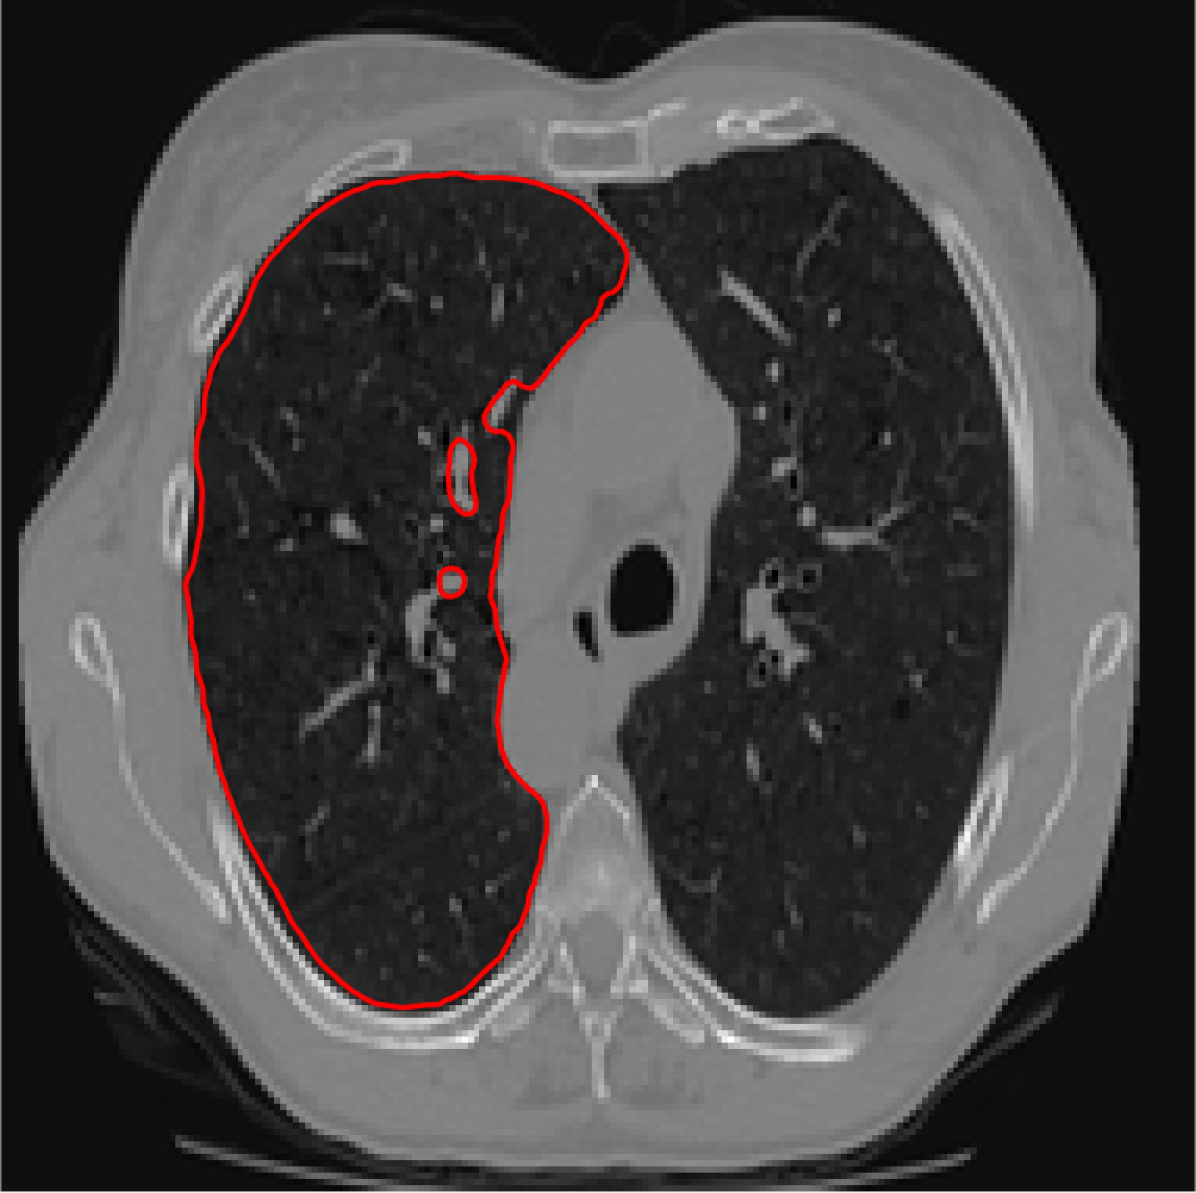

Figure 6: A sample result on the Liver data. We display the input image with the user input \mathcal{M}, the ground truth (GT) and results from the four methods. Moreover, we show comparisons with the model (4) solved in a variational framework with both Total Variation (TV) and Euler Elastica as explicit regularisation, as well as a comparison with the model solved in a Deep Image Prior framework.

Similarly we show some results in Figures 5 and 6 from the LiTS dataset of all the methods. Quantitative results of the 272727 images can be found in 2. Clearly for both datasets, M3 and M4 using the proposed ideas outperform M1 and M2, as well as methods using explicit regularisation (TV and Elastica), and the original DIP method.